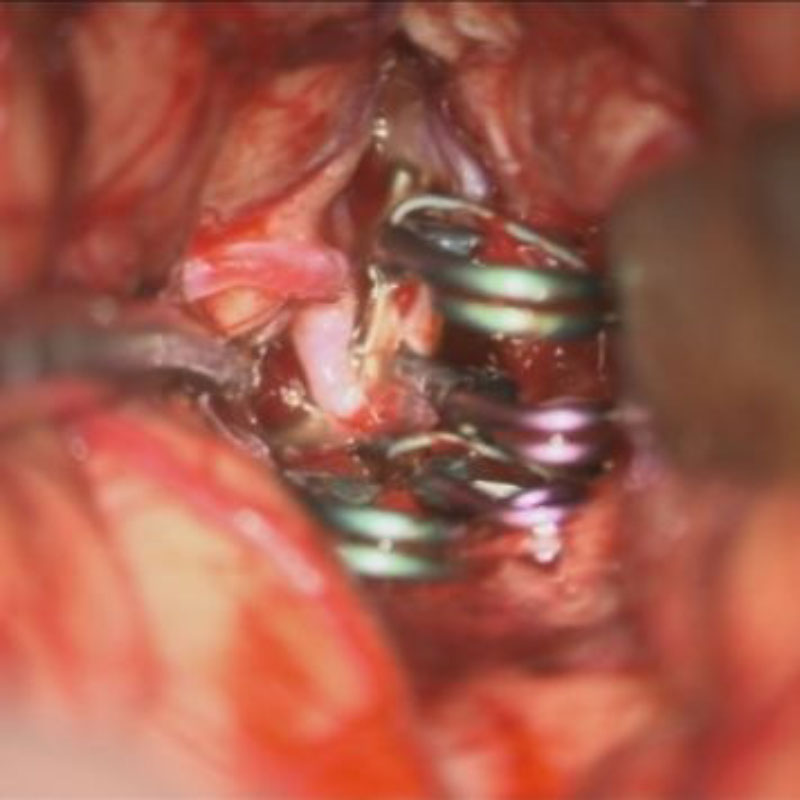

手術前

クリップ前

クリップ後

手術後